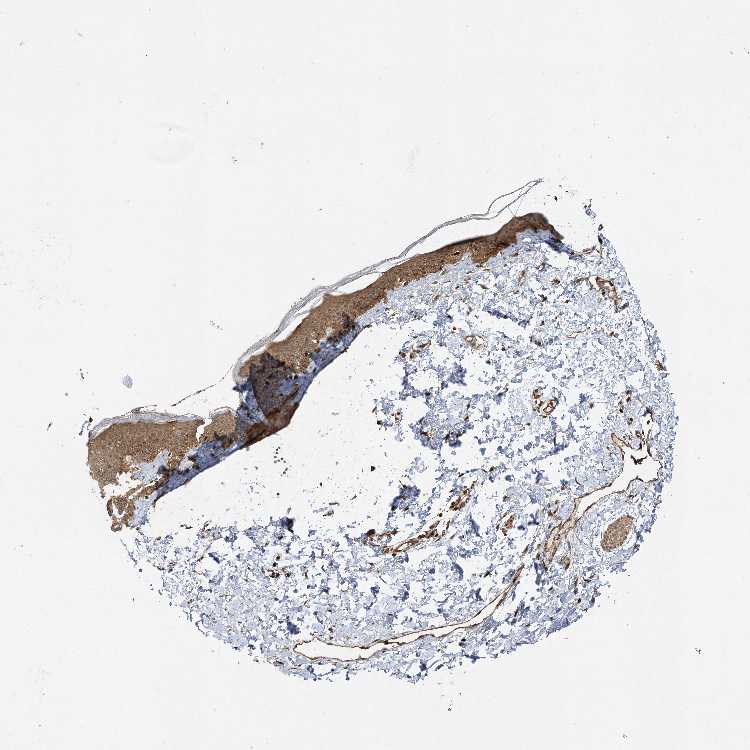

SKIN 2 - Antibody stainingi

Antibody staining in the annotated cell types in the current human tissue is reported as not detected, low, medium, or high, based on conventional immunohistochemistry profiling in selected tissues. This score is based on the combination of the staining intensity and fraction of stained cells.

Each image is clickable and will lead to virtual microscopy that enables deeper exploration of all samples and also displays staining intensity scores, fraction scores and subcellular localization as well as patient and tissue information for each sample.

Antibody HPA013162Antibody HPA036652Antibody CAB032830

Cells in basal layer -Medium-

Cells in corneal layer -Not detected-

Cells in granular layer -Medium-

Cells in spinous layer -Medium-

Endothelial cells -High-

Epidermal cells High-Medium

Extracellular matrix -Not detected-

Fibrohistiocytic cells -High-

Langerhans cells -Medium-

Lymphocytes -High-

Melanocytes -High-

Vascular mural cells -Not detected-